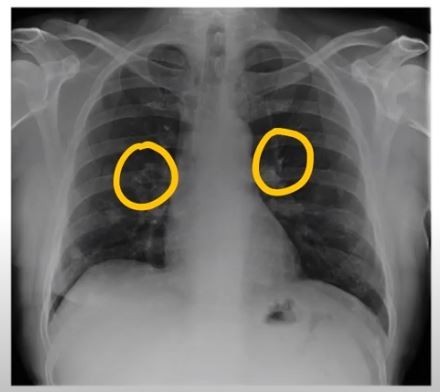

- 호흡 곤란 및 가슴 통증

- 설명: 폐렴의 가장 심각하고 중요한 증상입니다. 폐에 염증이 생겨 폐 기능이 떨어지면서 숨쉬기 힘들어지며, 얕고 빠른 호흡을 하게 됩니다. 심한 경우 가슴에 통증을 느끼거나, 옆구리가 결리는 듯한 느낌을 받을 수 있습니다.